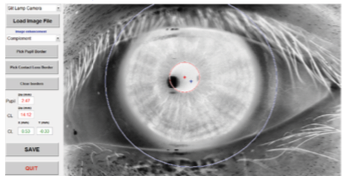

La técnica que se utilizó en el estudio para la evaluación del descentramiento fue mediante una fotografía de la adaptación de la lente para posteriormente ser procesada a través del programa MATLAB® (MathWorks, Inc. Natick, MA, USA), que se usó para determinar la diferencia entre el centro de la lente y el centro de la pupila.